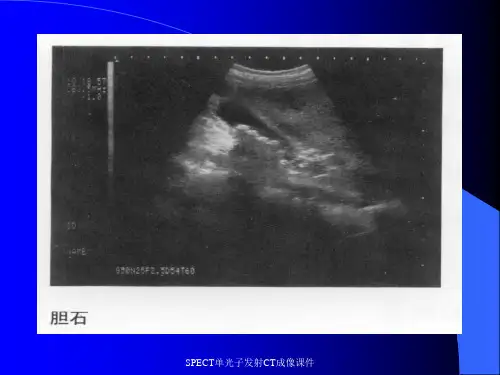

在临床应用中,单光子发射计算机断层成像技术常用于神经心理疾病、肺部疾病、甲状腺疾病、肝胆疾病、骨疾病等的检测和诊断,例如:肺气肿、脑血流量缺乏、血管瘤、甲状腺功能亢进、乳腺癌、骨肿瘤等。